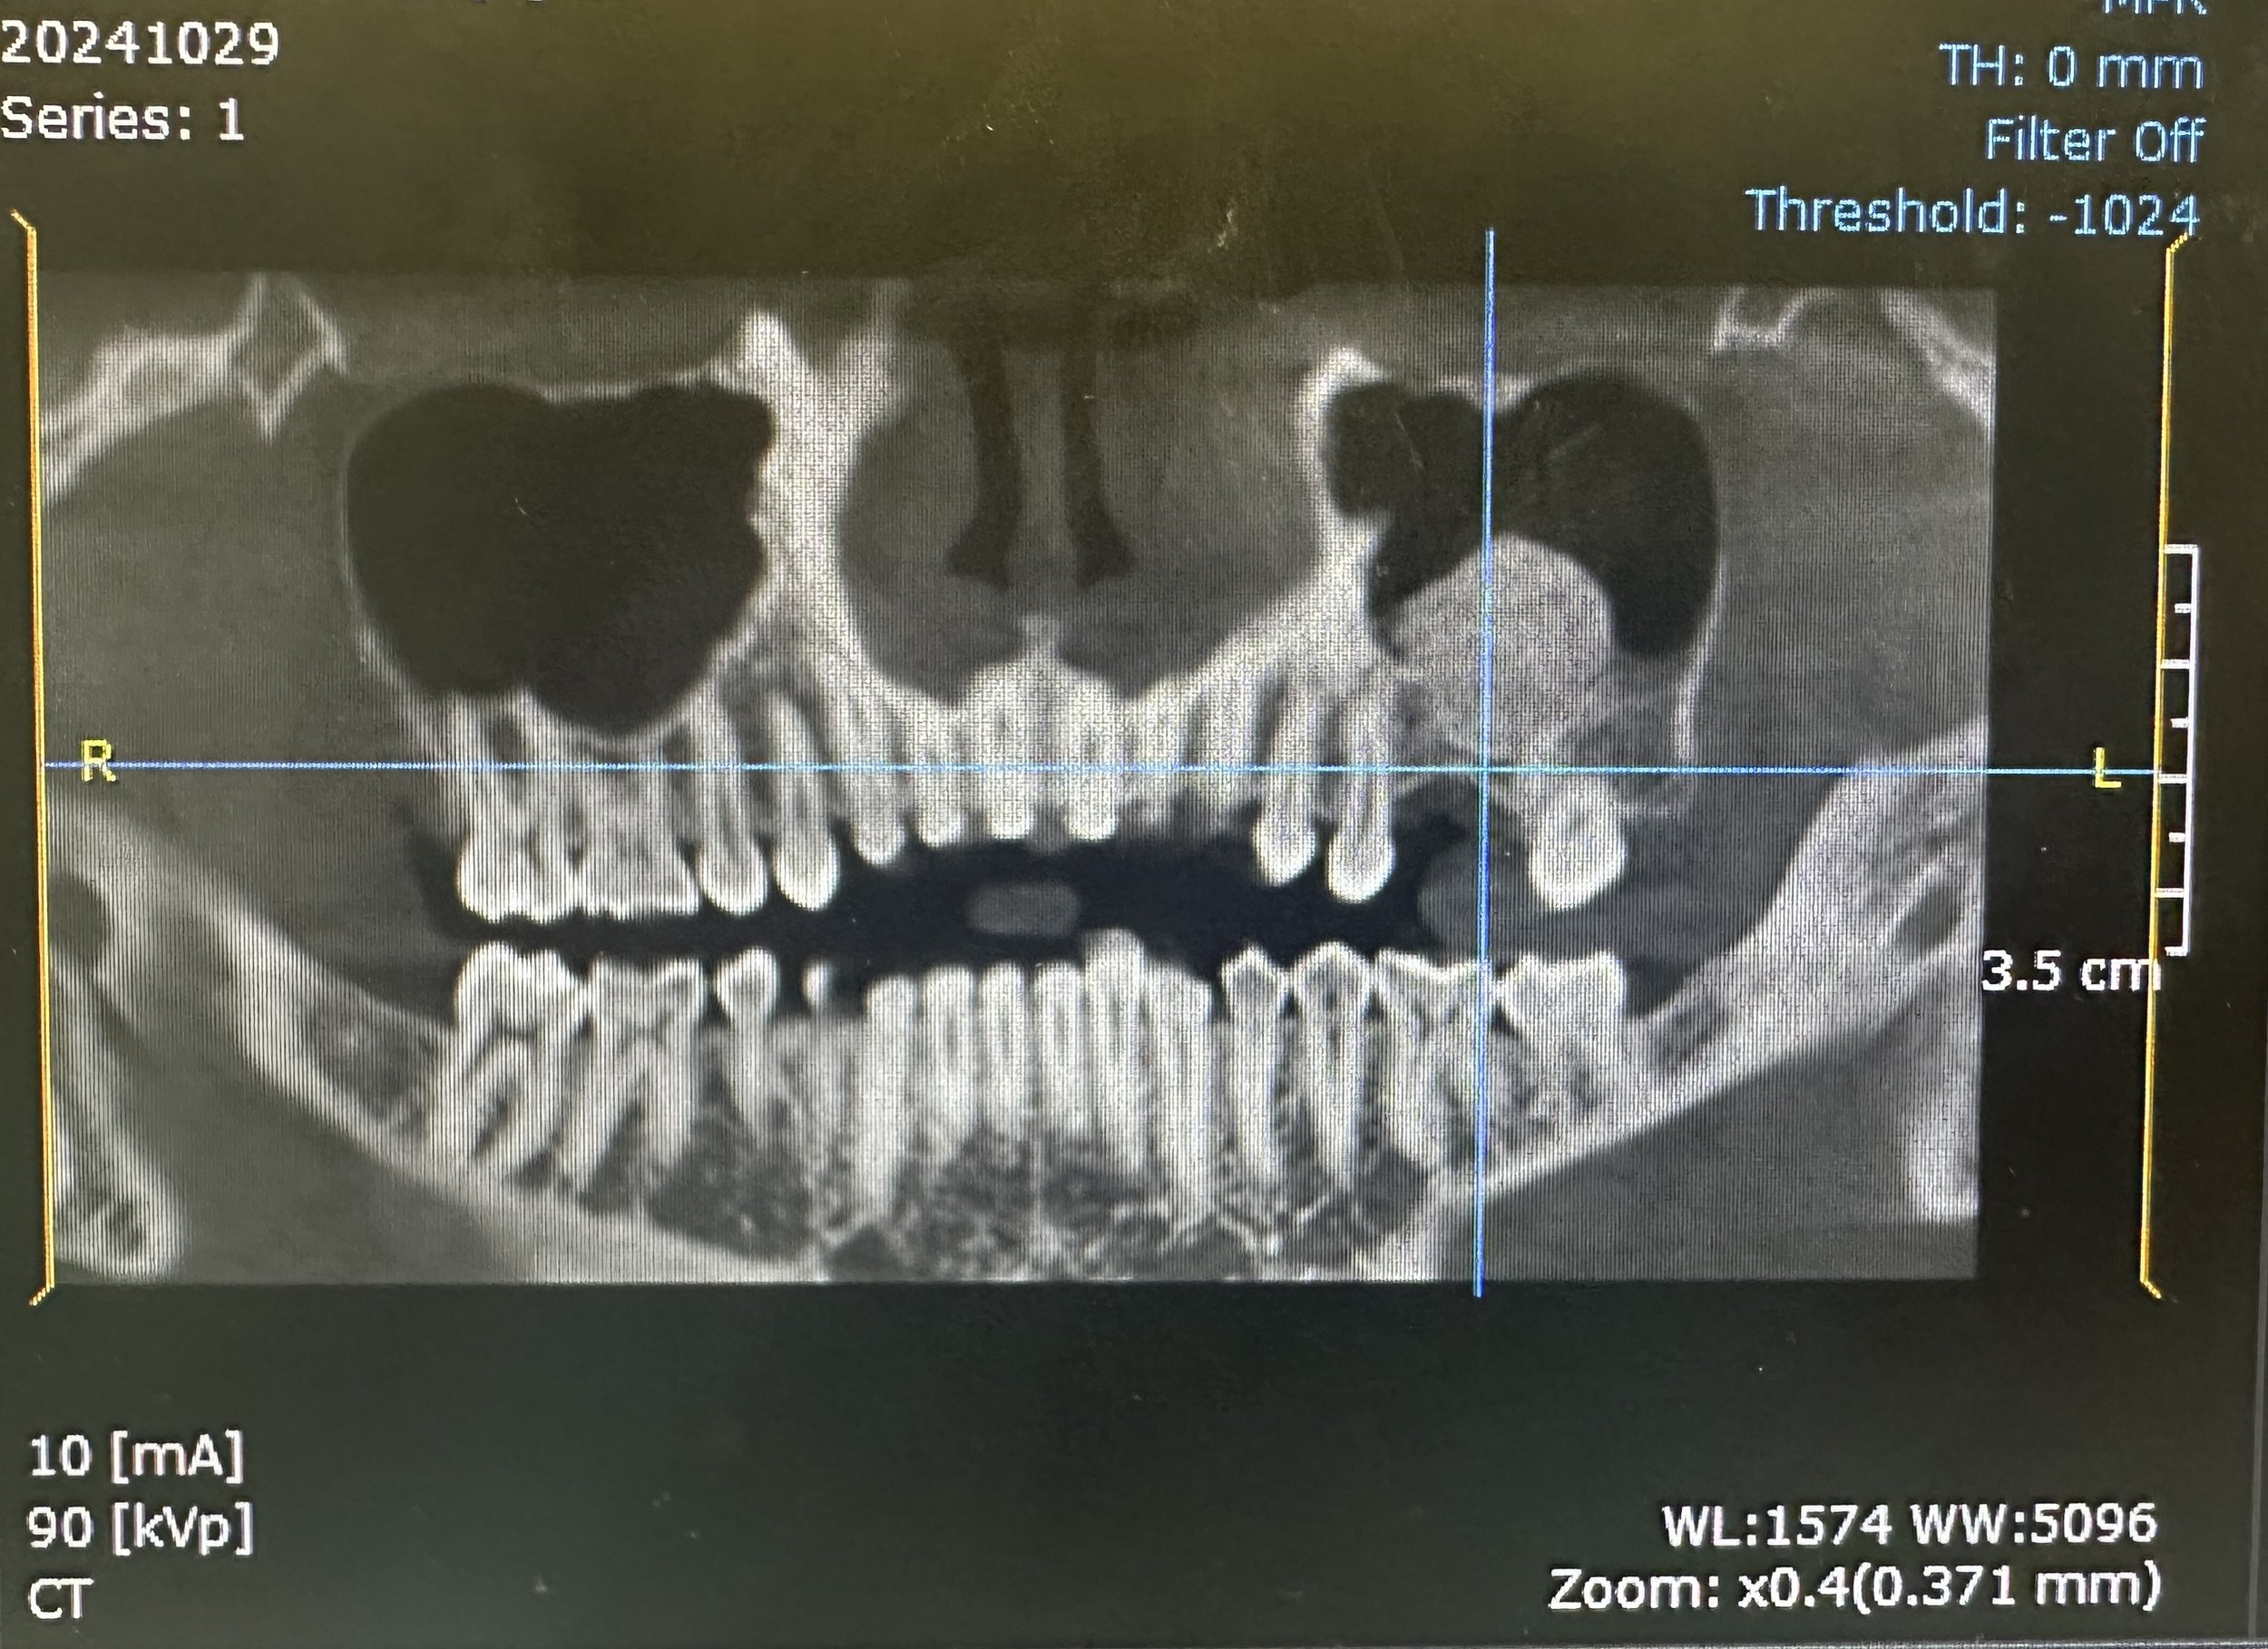

Following adequate healing and bone maturation, implant placement at site #14 was completed with improved structural support and optimal positioning. Post-operative imaging demonstrated successful bone regeneration and stable integration of the implant within the augmented site.